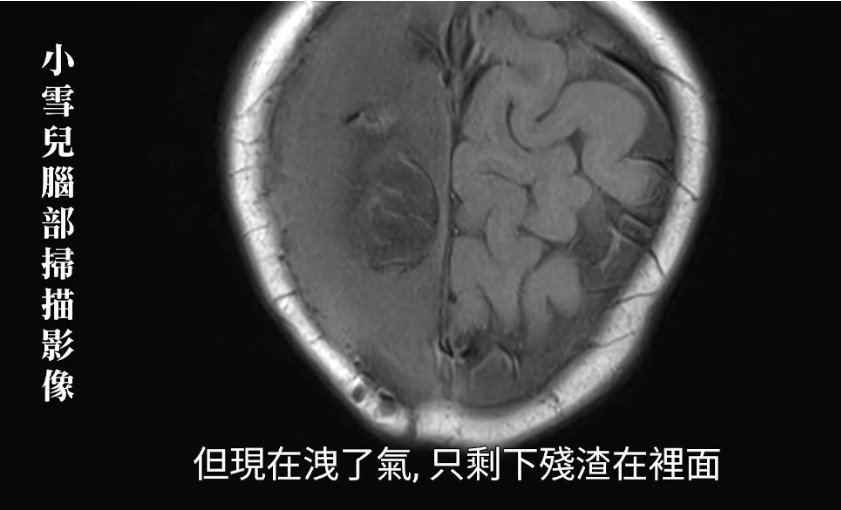

出事後,其實小雪兒的智能、學習能力都嚴重受損,聽醫生描述小雪兒大腦狀況,實在令人心傷,「醫生就話個腦本來一個氣球脹卜卜,但而家漏曬氣,得翻個殘渣喺入邊,即是,沒有了。右腦部分位置都受損,但醫生期望右邊腦未來可以取代左邊,我地就抱住呢個盼望,希望右邊真係可以做埋左邊的功能,將個不便減到最低!」